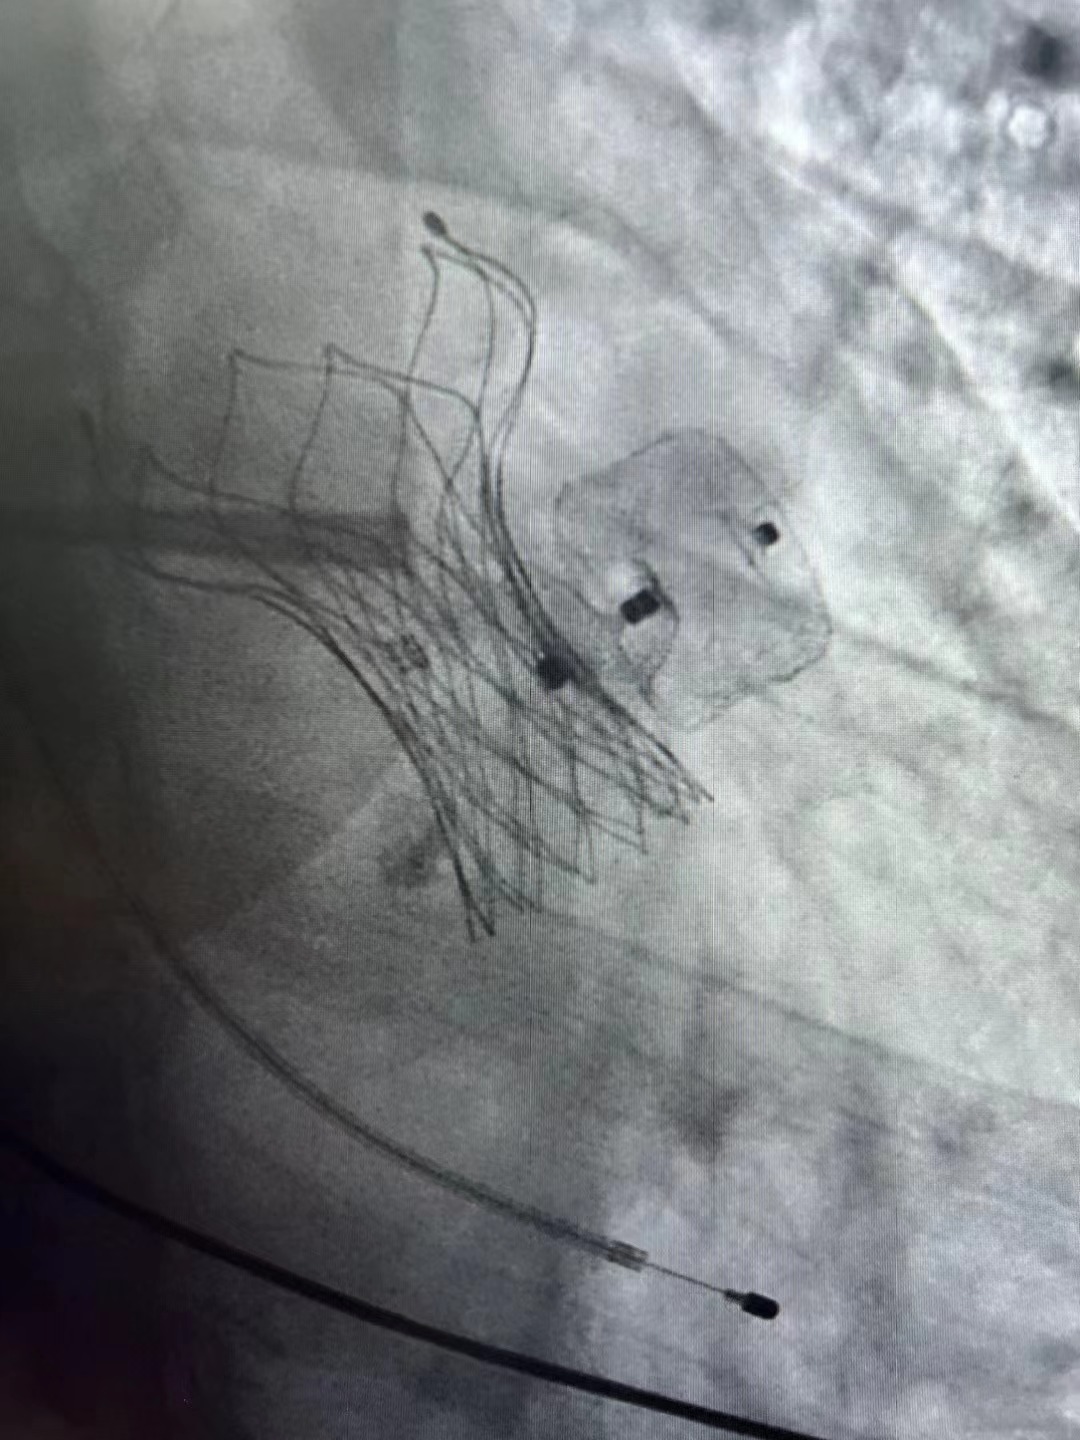

近日,西安交通大学第二附属医院心血管内科邓捷主任团队,在麻醉科、超声科等多个科室协同下,成功完成陕西省内首例一站式经导管主动脉瓣狭窄置换(TAVR)+左心耳封堵术(LAAC)。

患者是一位老年男性,近3年因心慌、胸闷,逐渐加重来我院就诊,其日常活动受到明显限制。近两年发生两次脑梗死,第一次脑梗遗留右侧肢体障碍,第二次又出现语言障碍,生活质量严重下降。心脏超声检查显示主动脉瓣膜重度狭窄并中量反流,二尖瓣大量反流,双心房增大,心电图呈持续性心房颤动。此患者不但急需解决主动脉瓣膜狭窄的问题,还需要降低远期再次出现脑梗死的风险。邓捷主任以患者切身利益出发,经过科室内讨论并与家属充分沟通后决定行一站式经导管主动脉瓣狭窄置换(TAVR)+左心耳封堵术。

患者情况特殊,面临多次脑梗病史遗留的肢体功能障碍、语言表达障碍、主动脉瓣口面积过小等诸多问题,为此次一站式手术增加了难度。团队医、护、技成员进行缜密的术前讨论,经过两个小时顺利完成手术。术后患者症状明显改善,韩东刚副主任医师复查超声结果显示瓣膜植入位置理想,二尖瓣反流也得到显著改善。术后第二日即返回普通病房,在病房护理人员悉心的活动指导下,于次日下地活动。

邓捷主任医师表示,TAVR手术是治疗高龄主动脉瓣狭窄的最佳选择,同时也是心内科前沿技术之一。团队既往成功开展各种复杂病例及首创病例,例如西北首例腋动脉脉入路TAVR、合并冠状动脉三支病变TAVR等。因接受TAVR手术的患者普遍高龄,所以常合并其他严重的心脑血管问题,一站式手术不但可以最短时间有效解决患者问题,还能减轻患者痛苦,减少住院时间,为患者带来了福音。此次邓捷主任团队成功完成陕西省首例一站式经导管主动脉瓣狭窄置换(TAVR)+左心耳封堵术(LAAC),标志着西安交大二附院心血管内科TAVR治疗技术迈向新高度,处于西北领先水平。